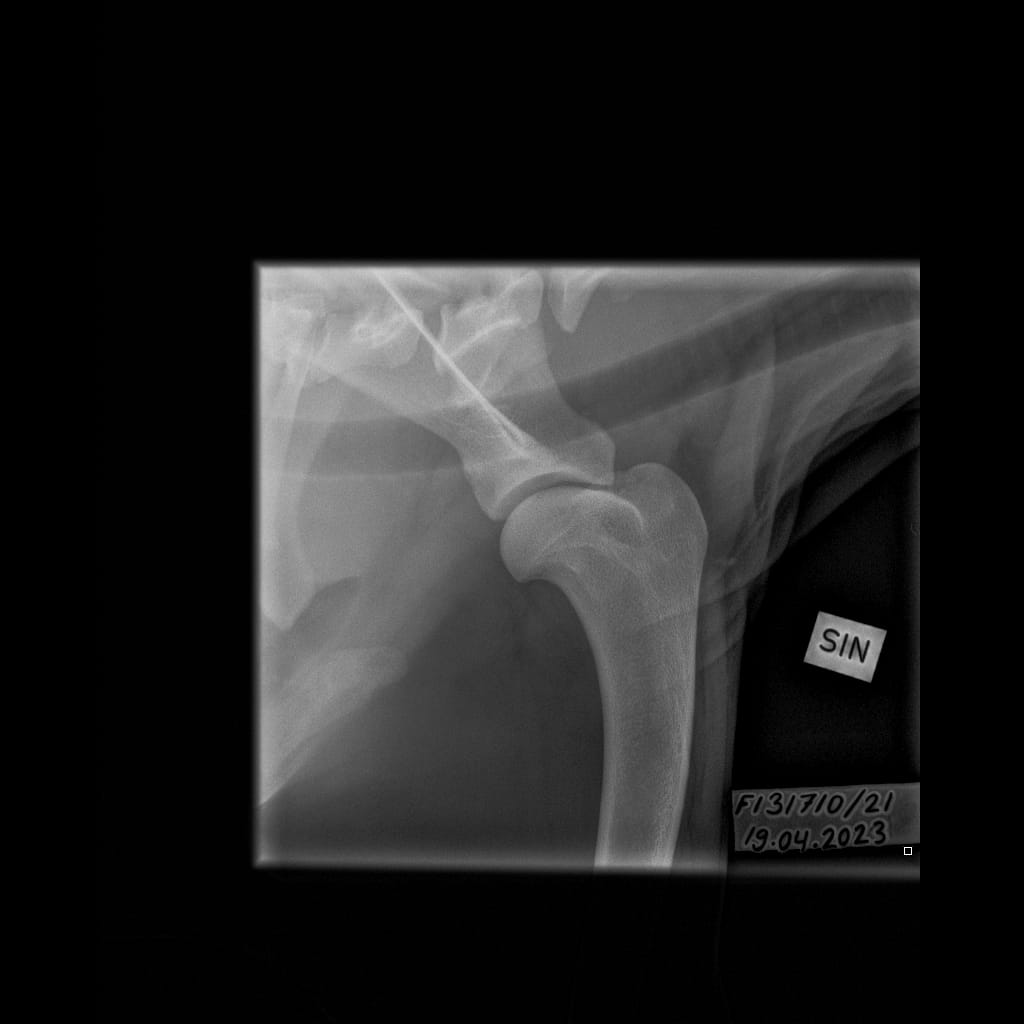

| Shoulders: | Unaffected/unaffected | ||

| Shoulders: | Unaffected/Unaffected |

| Shoulders: | Unaffected/Unaffected | |

| Shoulders: | Unaffected/Open to interpretation |